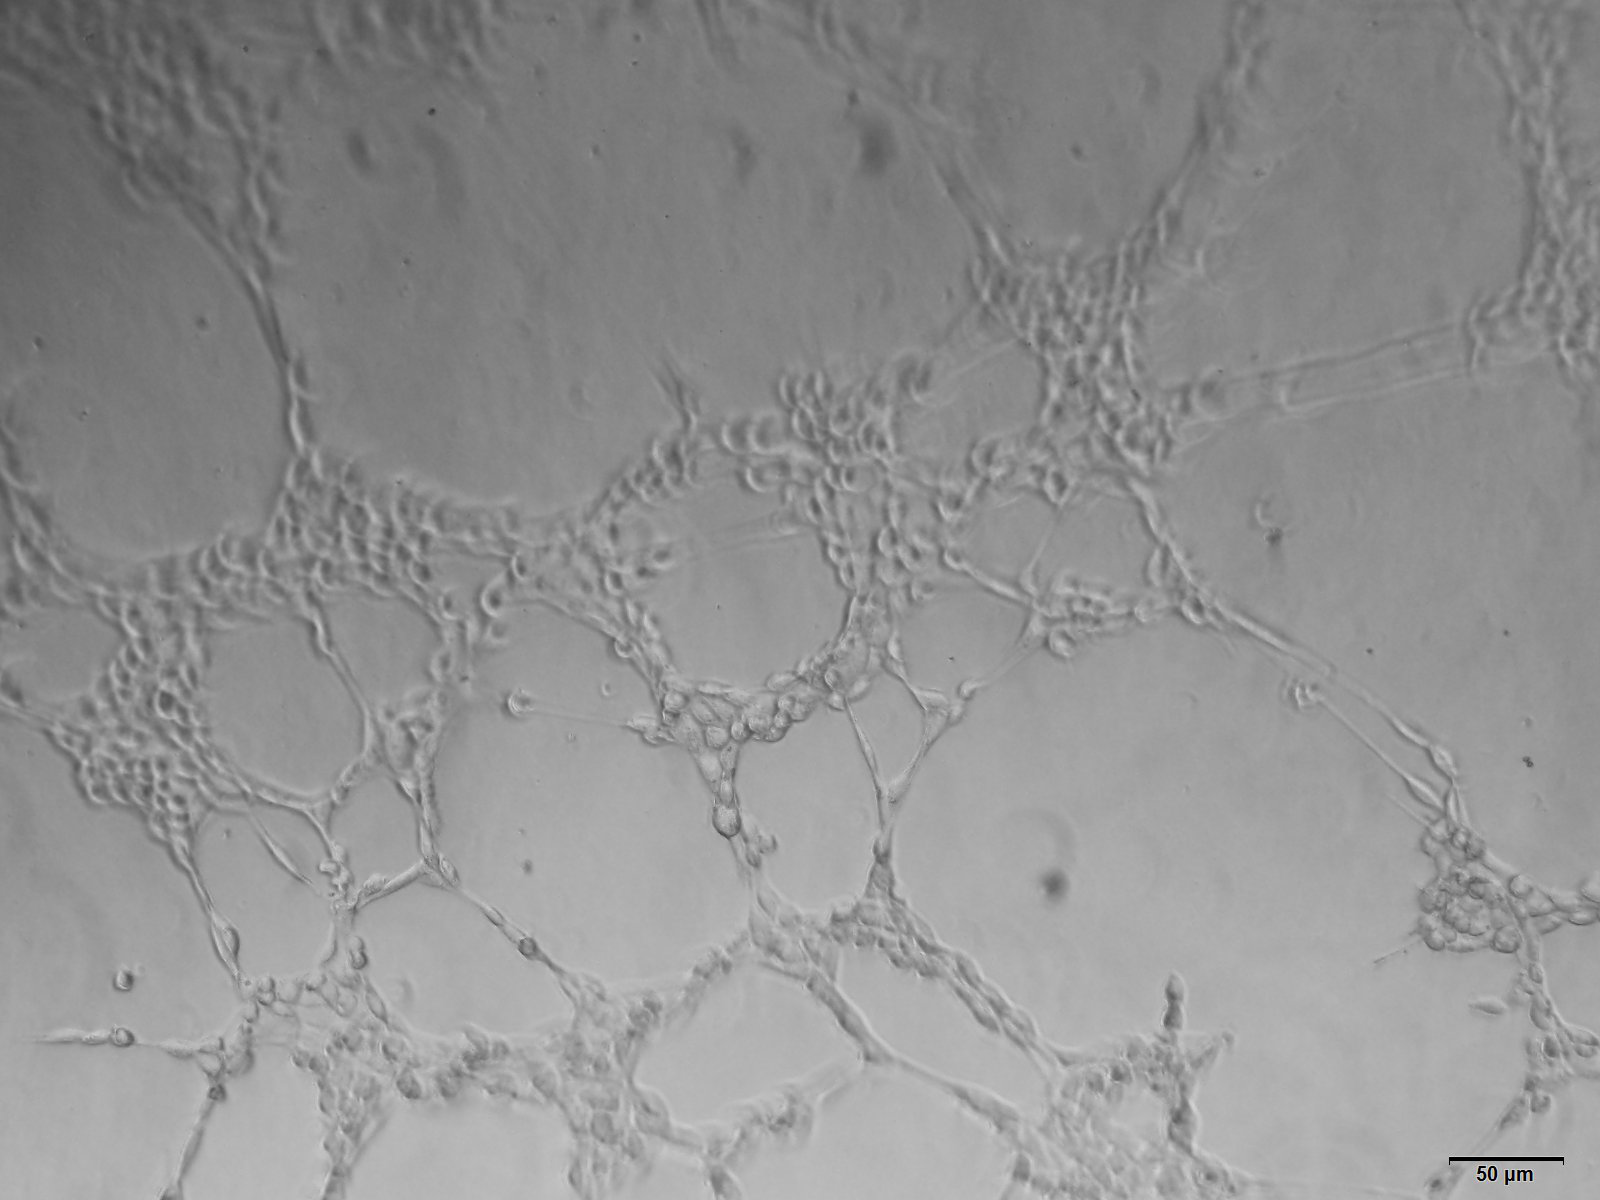

1. 体外实验:Matrigel小管形成实验,将HUEVC细胞接种于均匀铺好matrigel的培养皿中,将含有待测物的培养基或待测细 胞上清加入,根据细胞的生长速度实时观察HUEVC细胞是否成管,并对其成管长度、成环数目、结点数目及覆盖面积等进 行测量,并通过软件进行统计学分析,也可以根据需要,选择进行免疫荧光染色。

体外实验结果展示